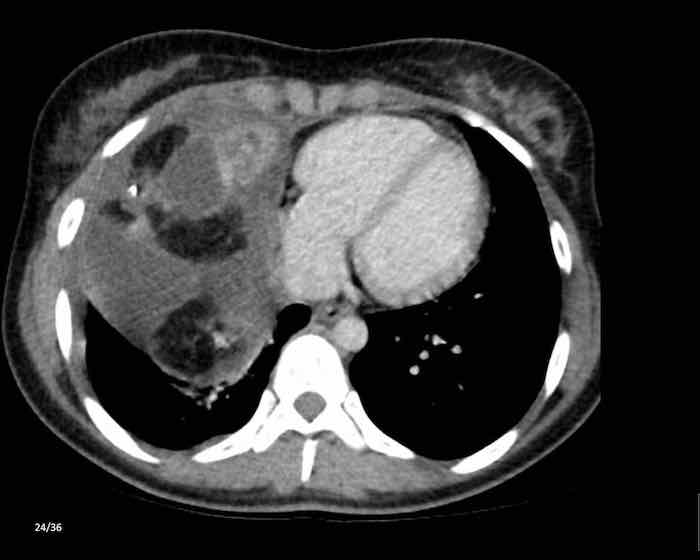

Các hình ảnh này của một nam giới 71 tuổi.

Trên CT ngực, tình cờ phát hiện một khối ở tuyến ức.

Hãy phân tích các hình ảnh. Nhận định của bạn là gì?

Hình ảnh

Một phần tổn thương có ngấm thuốc cản quang và có một số vôi hóa, có thể nằm ở thành nang.

Khi một tổn thương tuyến ức có thành phần đặc, nguyên tắc là… “khi còn nghi ngờ, hãy phẫu thuật cắt bỏ”.

Tổn thương đã được phẫu thuật cắt bỏ dựa trên kết quả CT và kết quả giải phẫu bệnh cho thấy đây là u tuyến ức dạng nang.